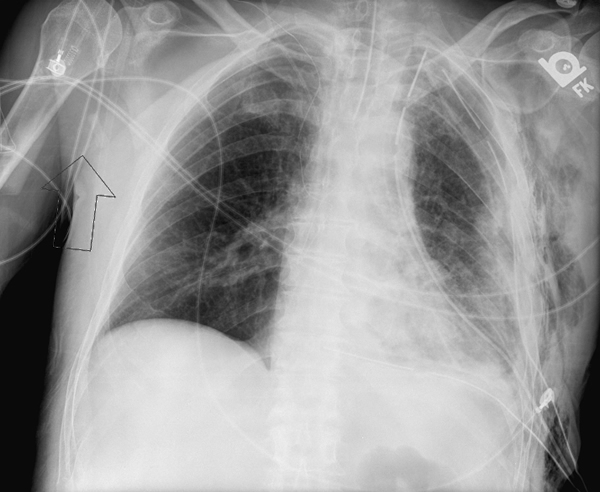

Figure 3. Postoperative chest radiograph after VATS decortication, with left pleural drainage tubes in place.

The chest tubes are maintained on suction to make sure there is complete lung expansion and adequate drainage of the pleural space (Figure 3). Once the drainage is less than 200cc/24hrs the tubes can be removed. For patients with an empyema, intravenous antibiotics are continued during the postoperative course and for a further 14 days of oral antibiotics once the patient is discharged. For patients with hemothorax, antibiotics are continued postoperatively for 48 hours.